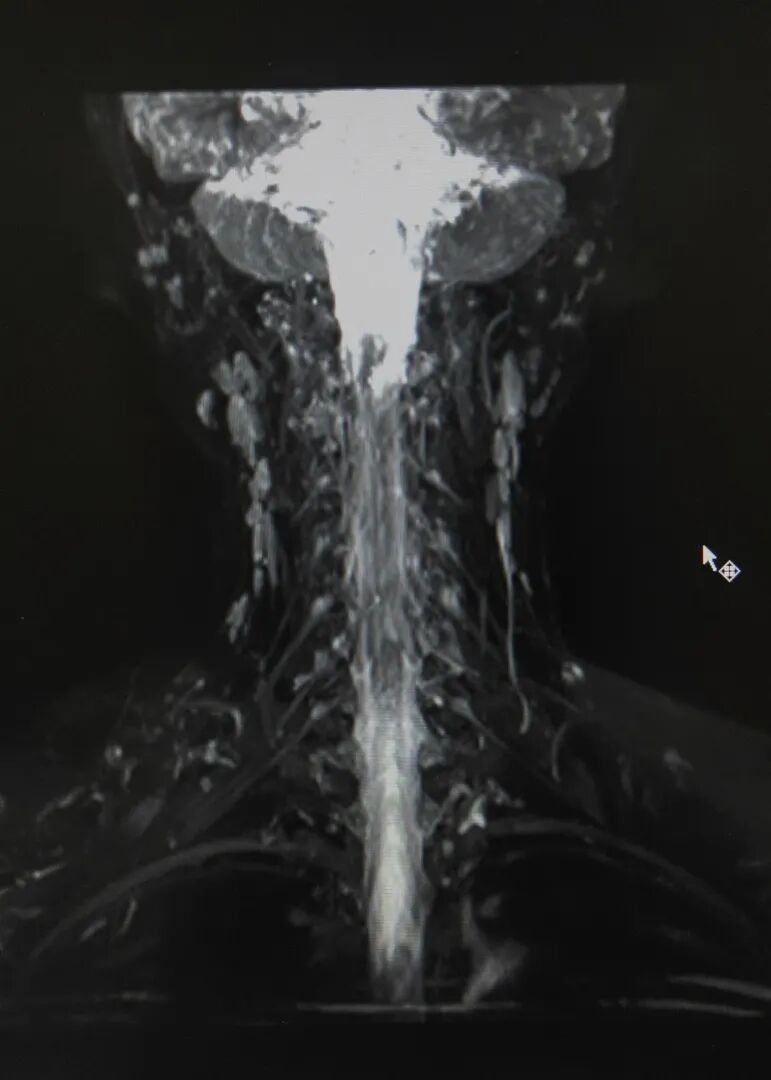

图片

臂丛神经

MR可以清晰显示臂丛神经全貌及周围结构关系,为创伤或肿瘤患者术前诊断及术后长期随访提供重要的信息,其在臂丛神经诊断中有不可替代的作用。

MRཡིས་དཔུང་པའི་དབང་རྩའི་རྣམ་པ་ཡོངས་དང་ཉེ་འཁོར་གྱི་སྒྲིག་གཞིའི་འབྲེལ་བ་གསལ་བོར་མངོན་ཐུབ།རྨས་སྐྱོན་ནམ་སྐྲན་ནད་ཕོག་མཁན་ལ་གཤགས་བཅོས་མ་བྱས་གོང་གི་བརྟག་དཔྱད་དང་གཤགས་བཅོས་བྱས་རྗེས་ཡུན་རིང་བཅར་འདྲི་བྱེད་པར་ཆ་འཕྲིན་གལ་ཆེན་མཁོ་འདོན་བྱེད་པ་དང་།དཔུང་ཚོམ་དབང་རྩའི་བརྟག་དཔྱད་ཁྲོད་ཚབ་བྱེད་མི་ཐུབ་པའི་ནུས་པ་ཡོད།